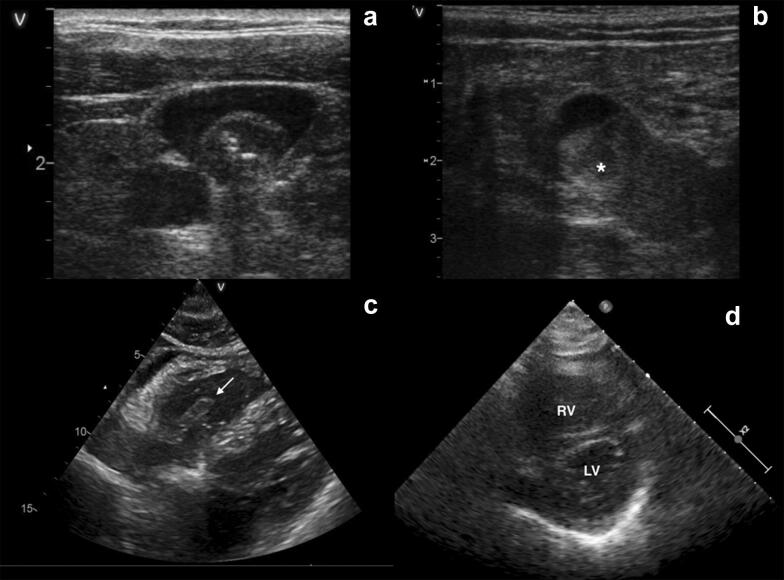

Fig. 1.

Ultrasound demonstration of thrombotic events in patients admitted with SARS-Cov2. Deep vein ultrasound showing (a—ESM1) the internal jugular vein with a thrombus surrounding a central catheter (central white point) and (b—ESM2) a thrombus of superficial and common femoral vein (white asterisk). Transthoracic echocardiography subcostal view demonstrating (c—ESM3) a thrombus in the right ventricular cavity, attached to the tricuspid valve (white arrow) and (d—ESM4) parasternal short axis view in patient with right ventricular dilatation (right ventricular/left ventricular area 0.7) inducing interventricular paradoxical septal motion